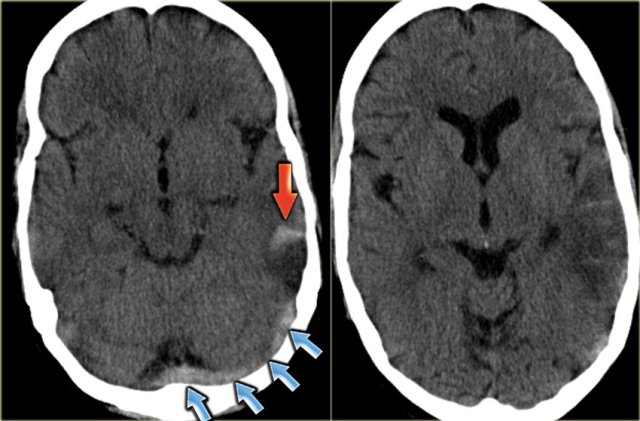

On the left images of a patient with a hemorrhagic infarction in the temporal lobe (red arrow).

Notice the dense transverse sinus due to thrombosis (blue arrows).

On the left images of a patient with hemorrhage in the temporal lobe.

When the hemorrhagic component of the infarction is large, it may look like any other intracerebral hematoma with surrounding vasogenic edema.

The clue to the diagnosis in this case is seen on the contrast enhanced image, which nicely demonstrates the filling defect in the sigmoid sinus (blue arrow).

On the left a similar case on MR.

There is a combination of vasogenic edema (red arrow), cytotoxic edema and hemorrhage (blue arrow).

These findings and the location in the temporal lobe, should make you think of venous infarction due to thrombosis of the vein of Labbe.

The next examination should be a contrast enhanced MR or CT to prove the diagnosis.